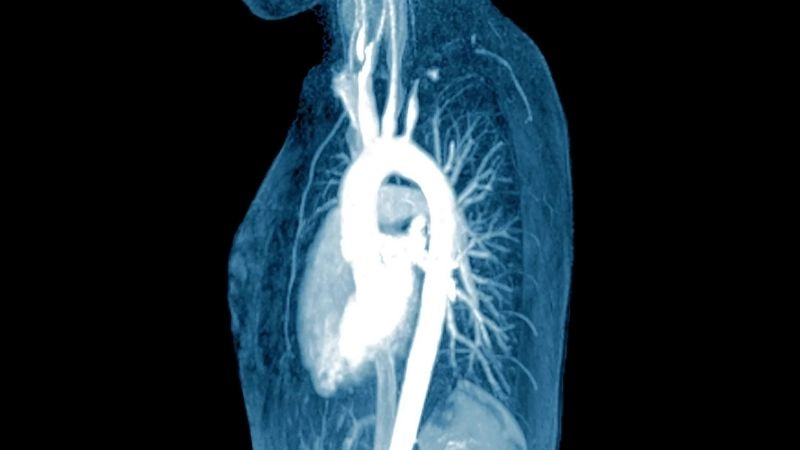

Images visual examples of Takayasu's arteritis

Takayasu's arteritis is a rare chronic inflammatory disease affecting large blood vessels, particularly the aorta and its branches, leading to narrowing and reduced blood flow.